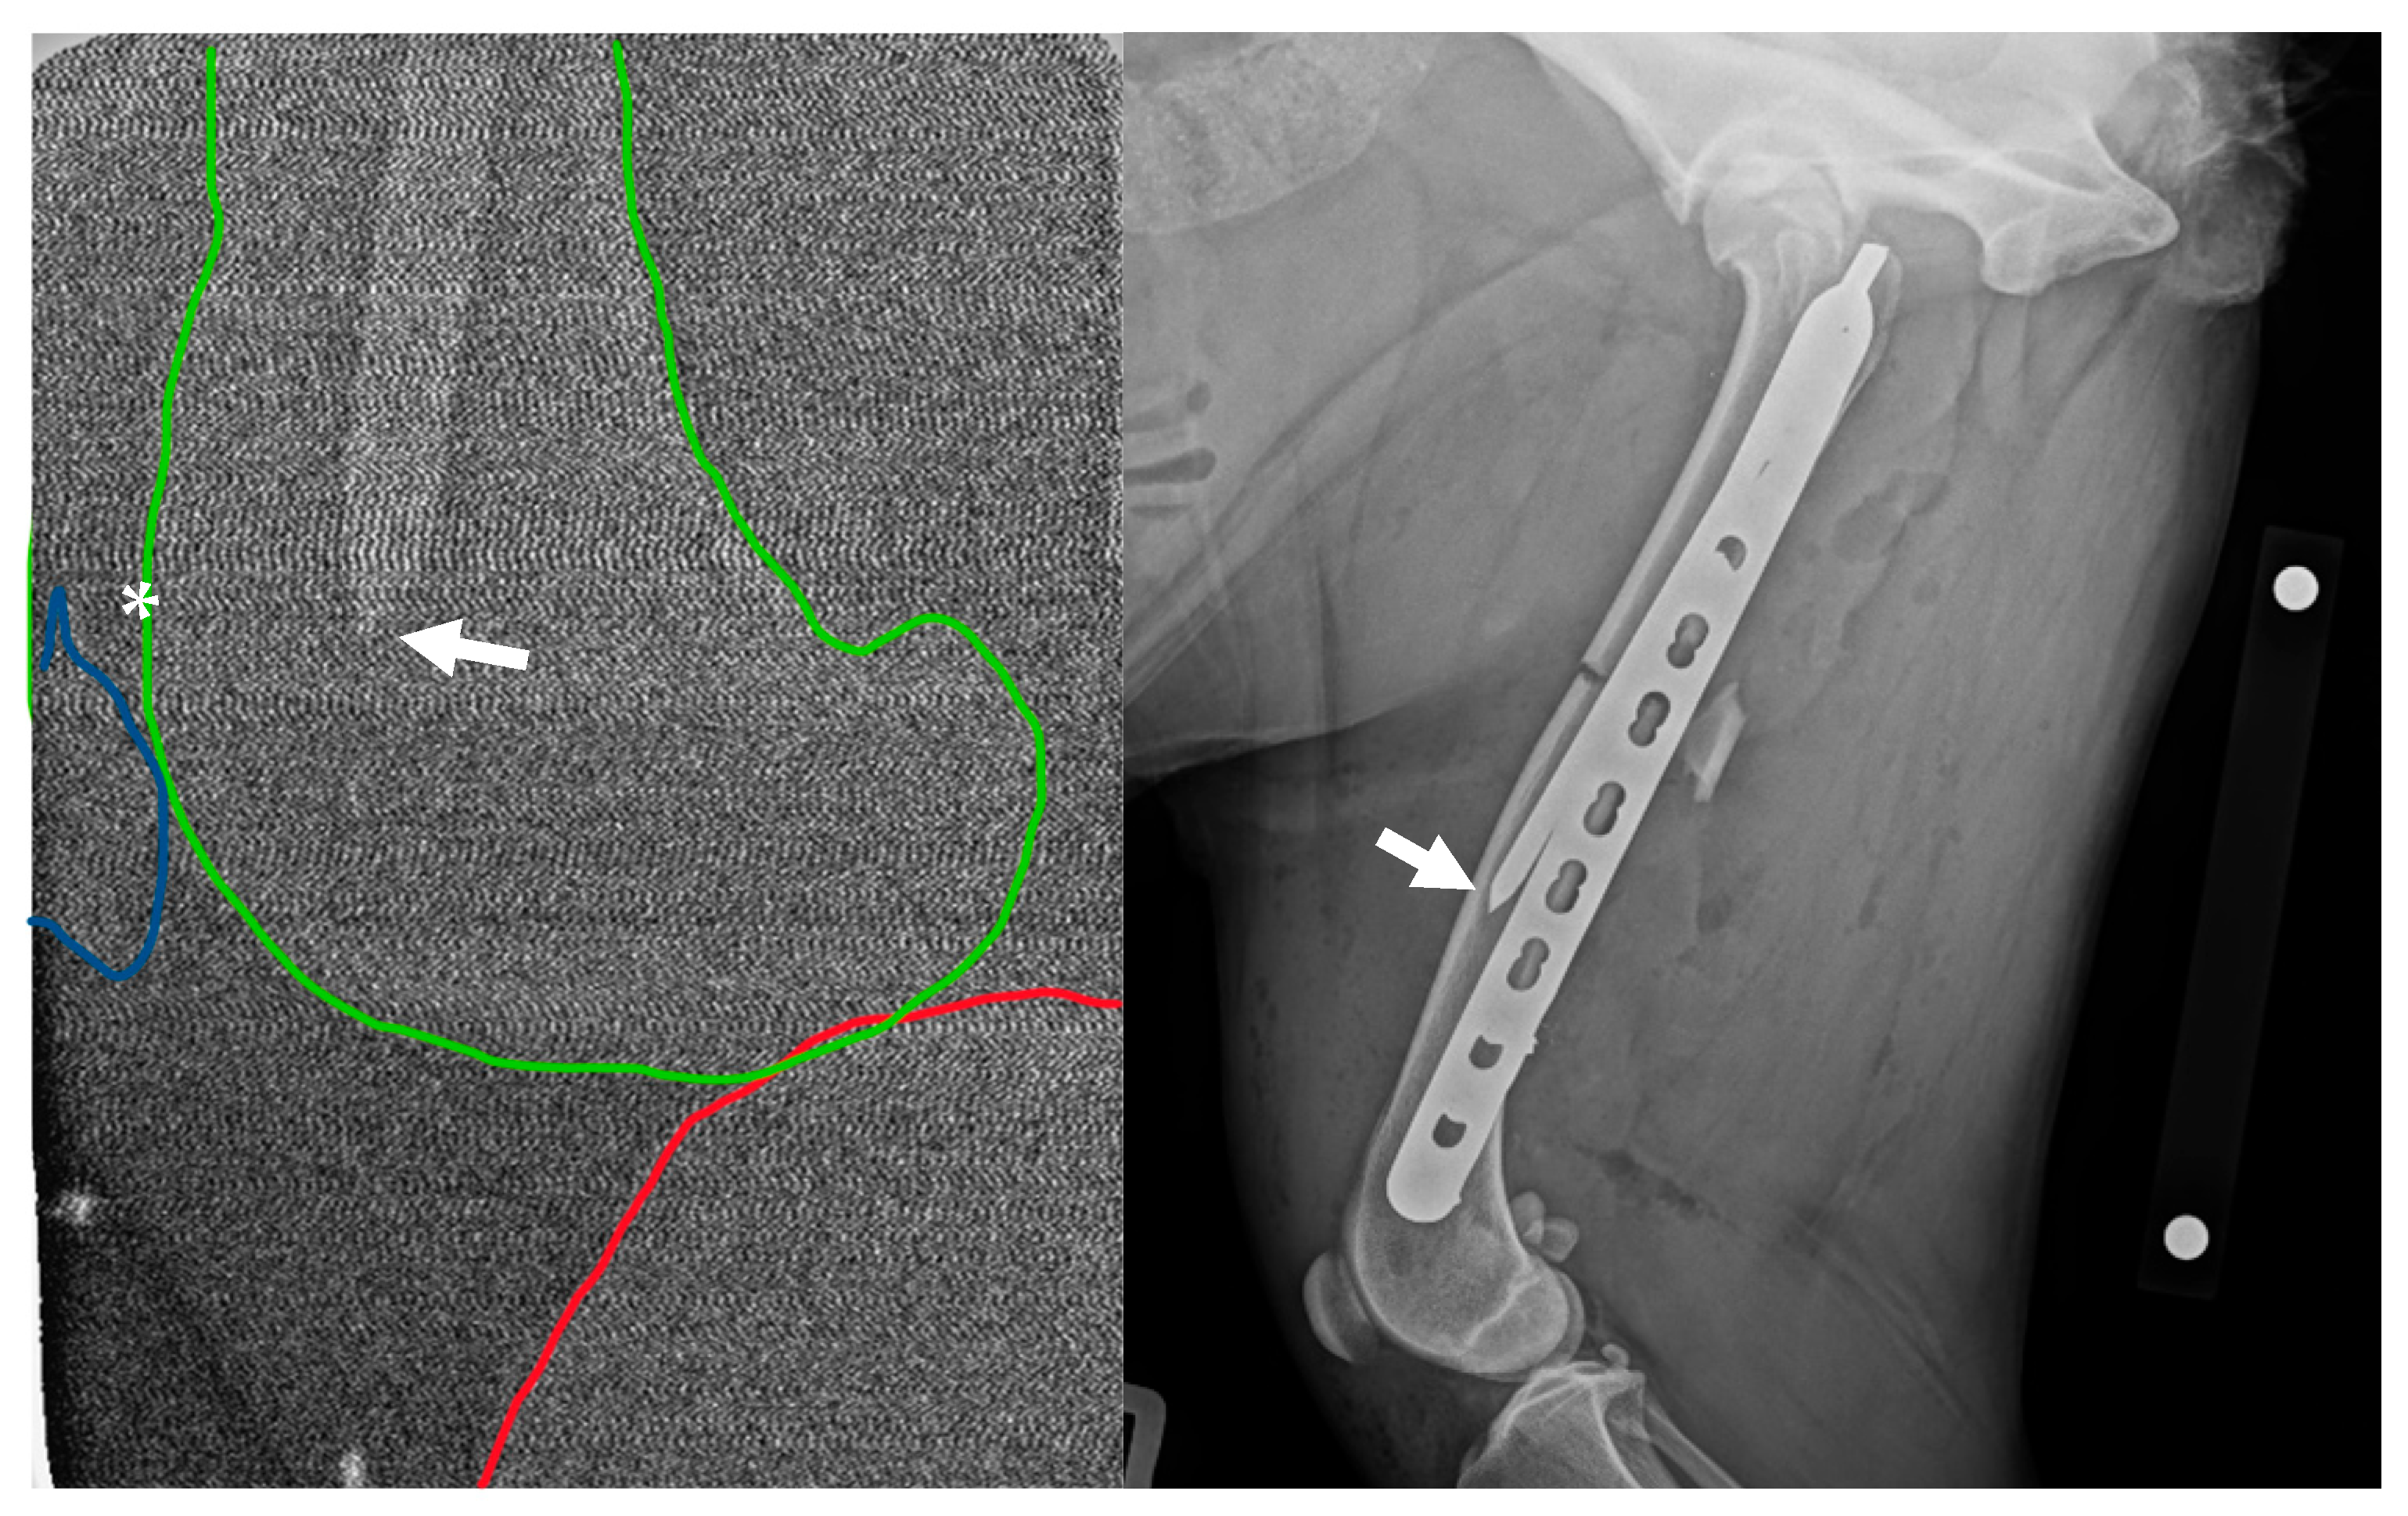

2.4. Post-Operative Imaging

2.5. Revision